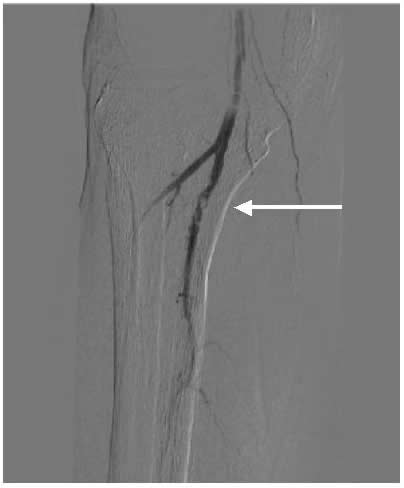

Case 2: A 74-year-old male with new onset severe claudication and threatened toes on the right side. An up-and-over wire was able to be advanced into the superficial femoral artery (but was totally occlusive). Cryoablation restored patency (Figure 2).

![]() |

| Figure 2 |